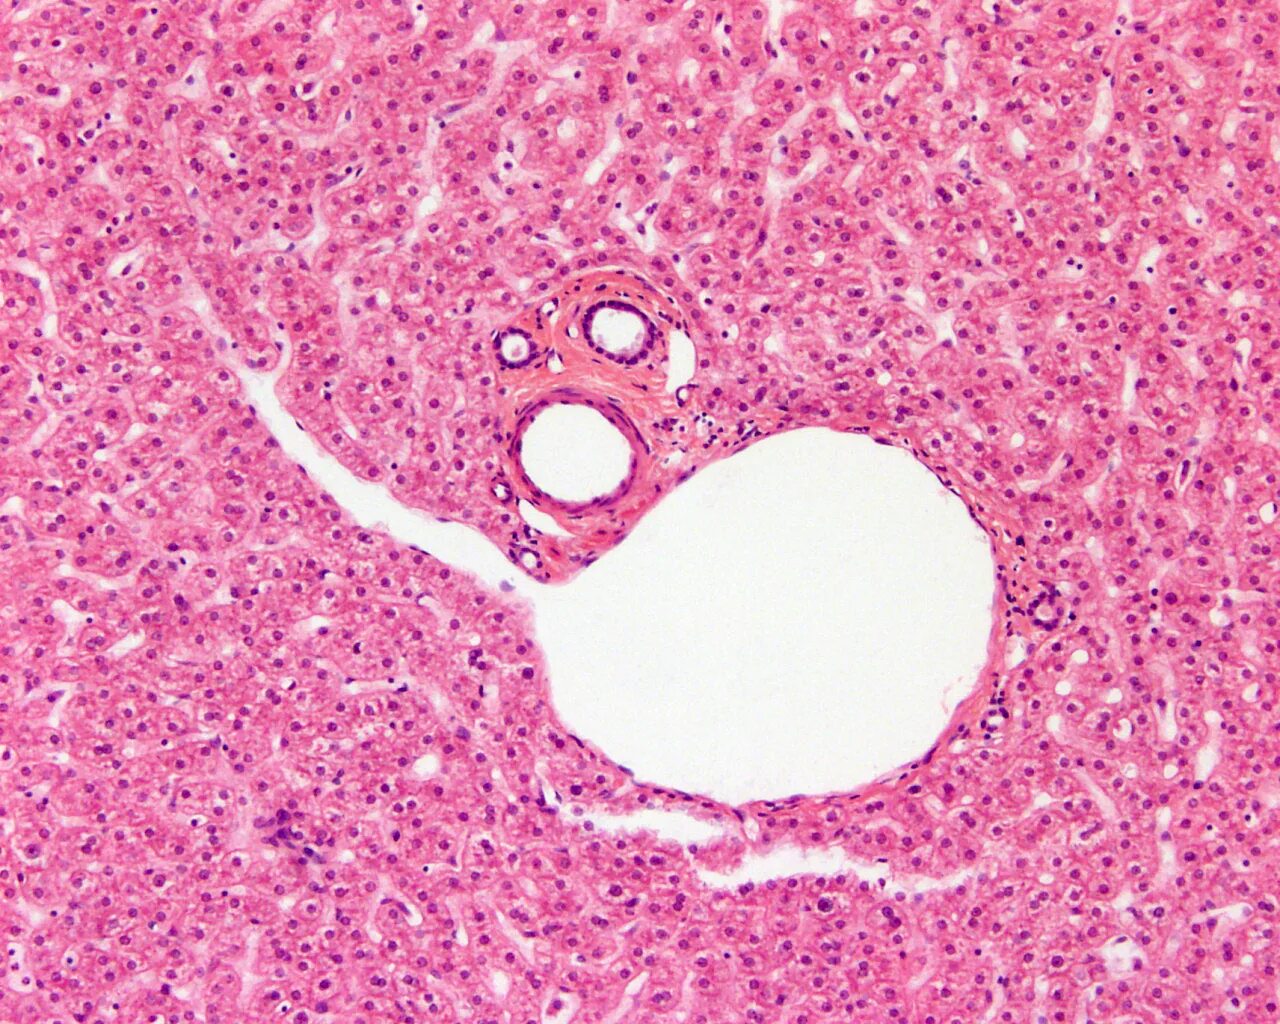

Печень гистологический